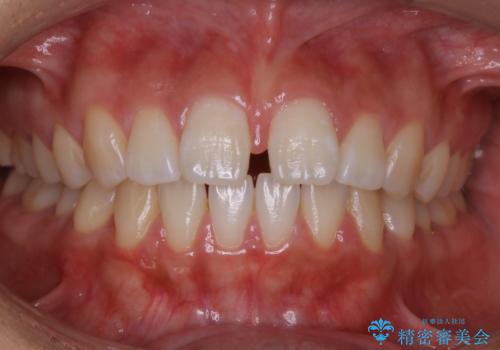

インビザライン矯正 前歯のすきっ歯を治したい

ラ行が言いにくい。